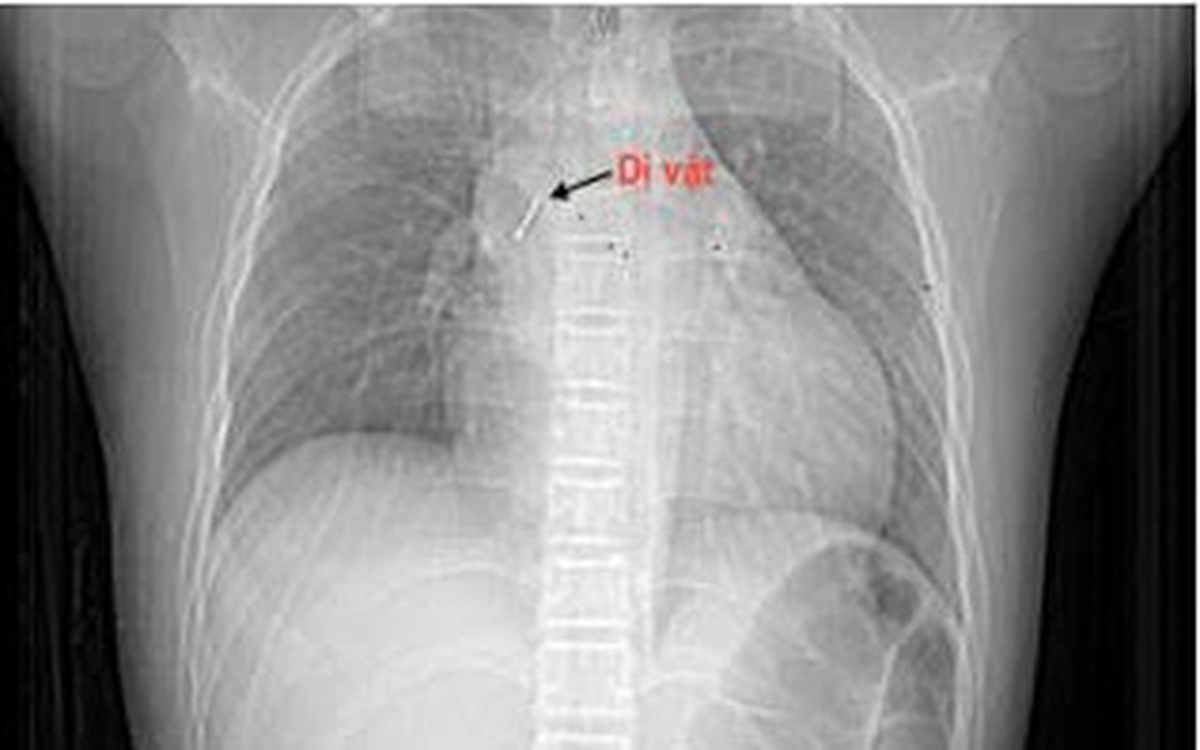

Theo gia đình bệnh nhi, vào tối ngày 13/10/2025, bé P.T.T.P (13 tuổi, Hà Nội) vừa ngồi xem điện thoại vừa ngậm chiếc đinh ghim bảng dài khoảng 2,5 cm. Trong lúc bé cười lớn, chiếc đinh bất ngờ rơi vào họng khiến bé ho sặc sụa, khó thở và cảm giác vướng ở ngực, nói khó. Gia đình hốt hoảng đưa trẻ tới bệnh viện gần nhà. Tại đây, bệnh nhi được làm các xét nghiệm máu, chụp phim cắt lớp vi tính lồng ngực, nội soi phế quản ống mềm, các bác sĩ xác định dị vật đã nằm sâu trong phế quản trung gian bên phải.

"Dị vật là chiếc đinh ghim sắc nhọn, nằm vướng tại phế quản trung gian, đầu nhọn đâm xuyên sâu vào thành phế quản. Đây là ca gắp dị vật rất khó, bởi ngoài tính chất, đặc điểm của dị vật như trên, bệnh nhi còn phản ứng theo phản xạ nên cần đòi hỏi thao tác nhanh, chính xác tuyệt đối để tránh làm rách thành phế quản hay đẩy dị vật xuống sâu hơn, có thể dẫn tới nhiễm trùng, chảy máu, tràn khí màng phổi, tràn khí trung thất. Thậm chí những biến chứng đó có thể gây hậu quả suy hô hấp cấp cho người bệnh. Do vậy sau khi đã đánh giá toàn diện kíp thực hiện đã cẩn trọng gỡ phần đầu đinh đang cắm vào thành phế quản thành trạng thái tự do bằng những dụng cụ kìm nội soi phế quản chuyên dụng, rồi từ từ gắp thành công dị vật ra ngoài. Quá trình diễn ra trong vòng 15 phút." bác sĩ Minh cho biết.